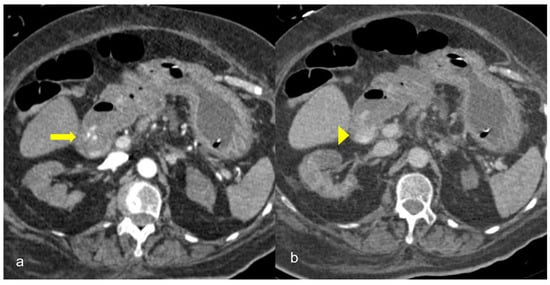

Figure 8. A 90-year-old COVID-19 patient presented acute right quadrant abdominal pain and cholestasis. Computed tomography on the axial (a) and coronal (b) plane showed acute cholecystitis with diffuse thickening of the gallbladder wall and pericholecystic fluid (arrowheads). Disruption of the gallbladder wall (arrow) is also present with fluid collection around the liver indicating perforation.